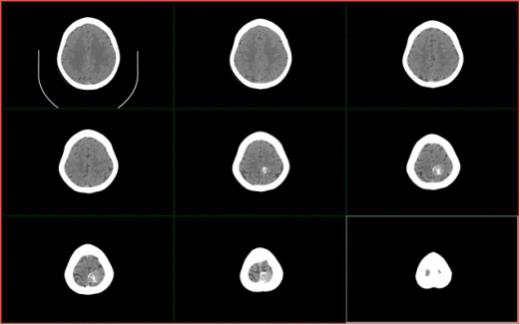

病例一:左基底节区脑出血

手术方法:简易立体定向经颞置管血肿引流术

、病例2:左颞叶大量出血

术前颅脑CT提示左顶部占位

术后颅脑CT提示左顶部占位切除